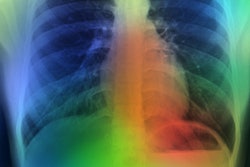

CHICAGO - A deep-learning model that predicts the 10-year risk of death from heart attack or stroke by using a single chest x-ray will be highlighted November 29 at the RSNA annual meeting in Chicago.

Weiss and colleagues wanted to test the potential of artificial intelligence (AI) in estimating 10-year cardiovascular risk from routine chest radiographs. They developed a deep learning model that was trained using 147,497 chest radiographs from 40,643 cancer screening trial participants and conducted independent testing in a separate cohort of 11,430 outpatients who were potentially eligible for intervention.

The team concluded that deep learning could estimate cardiovascular risk from a routine x-ray image similar to the current clinical standard.